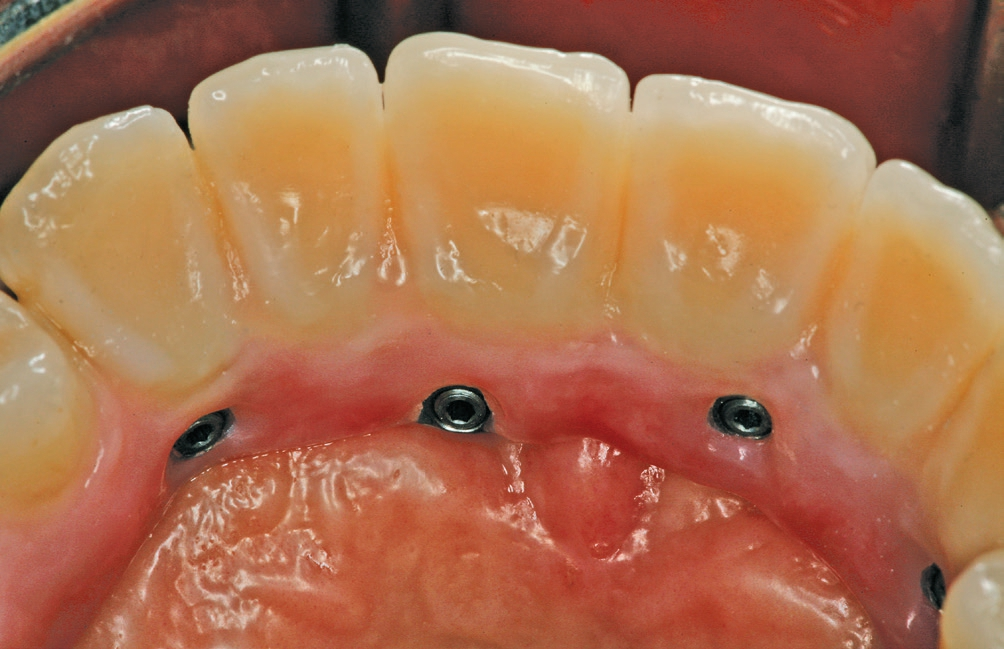

Das Aufschrauben der definitiven Brücke gestaltete sich problemlos. Nach Abnahme der temporären Versorgung ist die fertiggestellte Brücke über die Prothetikkappen bzw. die Verbolzungen auf den Implantaten befestigt worden (Abb. 5 und 6). Bei den posterioren Implantaten wurde der Schraubenzugang vom Zahntechniker nach vestibulär – außerhalb des sichtbaren Bereichs – gelegt (Abb. 7 und 8). Die anderen Implantate wurden im palatinalen Bereich verschraubt (Abb. 9). Aufgrund der Drei-Punkt-Fixierung ist ein Verkippen oder das Rotieren des Zahnersatzes ausgeschlossen. Da die Schraube in der Sekundärkonstruktion „gefangen“ ist, wird die Anwendung im Mund erleichtert. Ein lästiges Einfädeln entfällt. Bereits mit zwei bis drei Umdrehungen ist eine Schraube fixiert. Weder ästhetisch noch funktionell treten Beeinträchtigungen auf.

Abschließend wurden die funktionellen, ästhetischen und parodontal- hygienischen Faktoren überprüft und dem Patienten entsprechende Hinweise zur adäquaten Reinigung des Zahnersatzes gegeben (Abb. 10 und 11). Bei einem regelmäßigen Recall (idealerweise aller drei Monate) kann die Brücke aufgrund der transversalen Verschraubung sehr einfach gelöst und alle erforderlichen Mundhygienemaßnahmen vorgenommen werden.

Ein weiterer wesentlicher Vorteil ist das einfache Handling beim Lösen und Befestigen der prothetischen Restauration in der Zahnarztpraxis. Im Idealfall erfolgt ein dreimonatiger Recall. Bei diesem Termin kann die geschulte zahnärztliche Assistenz die verschraubte Brücke einfach von den Implantaten lösen und in das Reinigungsbad legen. Bei einer okklusalen Verschraubung ist dies deutlich zeitaufwändiger, weswegen ein Abschrauben häufig nur einmal pro Jahr vorgenommen wird.

Die transversale Verschraubung innerhalb des SKY fast & fixed-Systems (bredent medical) bietet eine einfache und sichere Möglichkeit der Rehabilitation des zahnlosen Kiefers, ohne Einschränkungen – wie deutlich sichtbare Schraubenkanäle – in Kauf nehmen zu müssen. Je nach Implantataustritt kann durch die transversale Verschraubung der Schraubenzugang aus dem sichtbaren Bereich verlegt werden. Dem Zahnarzt ist ein einfacher Zugang zur Entnahme des Zahnersatzes möglich.